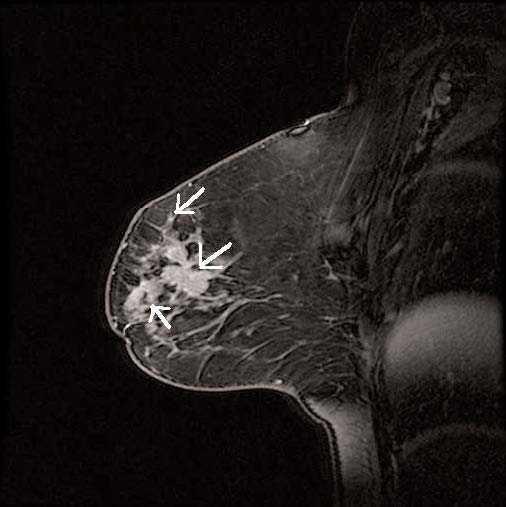

Con la RM mamaria preoperatoria, además de delimitar con mayor exactitud la extensión del tumor, tratamos de buscar lesiones multifocales, multicéntricas o en la mama contralateral que no se hubiesen visto en el estudio mamográfico y ecográfico previos. Se define como lesiones multifocales aquellas separadas de la lesión principal menos de 4 cm y situadas en el mismo cuadrante (fig. 1); como multicéntricas aquellas lesiones situadas en diferentes cuadrantes del de la lesión principal o separadas más de 4 cm (fig. 2), y como bilaterales aquellas lesiones que aparecen en la mama contralateral a la lesión principal.

Figura 1. Imagen de carcinoma multifocal.